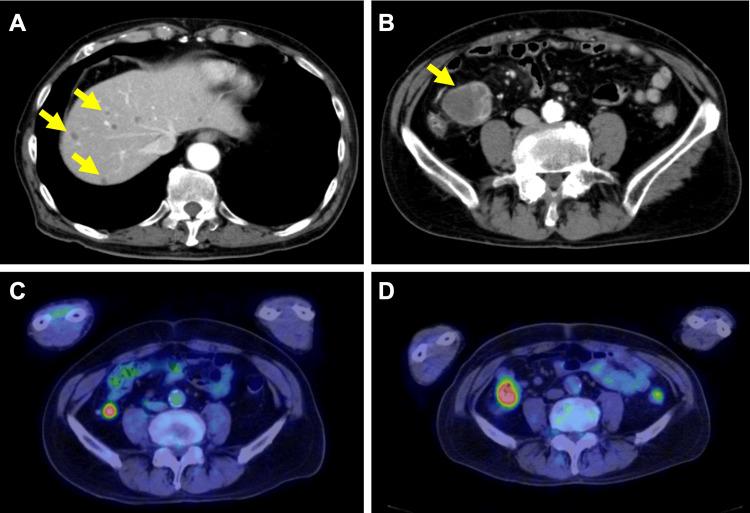

SMARCA4-deficient undifferentiated tumor (SMARCA4-UT) is a rare and aggressive malignancy characterized by the loss of SMARCA4 protein expression. It typically affects middle-aged male smokers and has a poor prognosis due to its rapid progression and metastatic potential. This case report presents a 73-year-old male diagnosed with a thoracic SMARCA4-UT. Initially diagnosed with stage IVA non-small cell lung cancer, the patient underwent brain tumor resection, radiation, and chemo-immunotherapy. Treatment was halted due to immune-related adverse events. During treatment, a progressing small intestine tumor was discovered, resected, and identified as SMARCA4-UT metastasis through immunohistochemistry, leading to a revised diagnosis of SMARCA4-UT with brain and small intestine metastases. The patient received multimodal treatment, including surgery, radiation, and chemo-immunotherapy. The small intestine metastasis showed resistance to systemic therapy, necessitating surgical intervention. This case highlights the diagnostic challenges and treatment complexities of SMARCA4-UT, emphasizing the importance of comprehensive diagnostic workup and personalized treatment strategies. It demonstrates the potential efficacy of combining systemic therapy with targeted interventions for oligoprogressive disease. The patient's progression-free survival at approximately two years post-diagnosis underscores the need for further research into optimal management strategies for this rare tumor.

SMARCA4缺陷型未分化肿瘤(SMARCA4-UT)是一种罕见的侵袭性恶性肿瘤,其特征是SMARCA4蛋白表达缺失。它通常影响中年男性吸烟者,由于其快速进展和转移潜能,预后较差。本病例报告介绍了一名73岁男性,被诊断为胸部SMARCA4-UT。该患者最初被诊断为IVA期非小细胞肺癌,接受了脑肿瘤切除、放疗和化学免疫治疗。由于免疫相关不良事件,治疗中断。在治疗期间,发现了一个进展性小肠肿瘤,将其切除,并通过免疫组织化学鉴定为SMARCA4-UT转移,从而将诊断修订为伴有脑和小肠转移的SMARCA4-UT。患者接受了多模式治疗,包括手术、放疗和化学免疫治疗。小肠转移瘤对全身治疗耐药,需要进行手术干预。本病例突出了SMARCA4-UT的诊断挑战和治疗复杂性,强调了全面诊断检查和个性化治疗策略的重要性。它证明了将全身治疗与针对寡进展性疾病的靶向干预相结合的潜在疗效。患者在诊断后约两年的无进展生存期强调了对这种罕见肿瘤的最佳管理策略进行进一步研究的必要性。